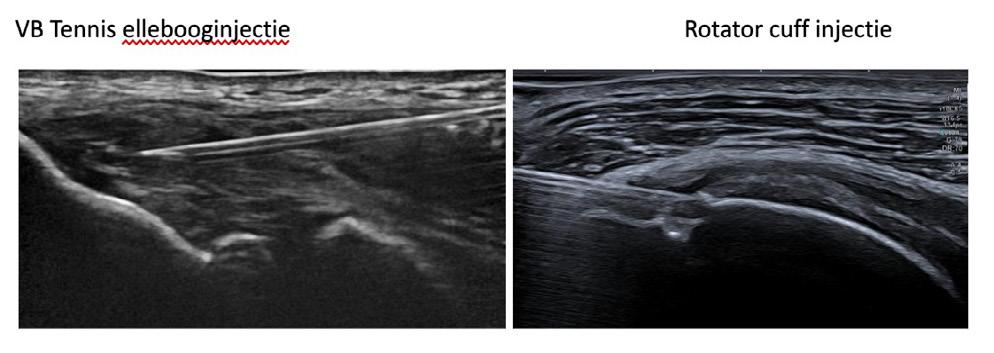

2. Therapie resistente tendinopathiën al dan niet met fissuren of partiële scheur

Studies tonen aan dat PRP de functionele activiteit verbetert en pijn vermindert. De injectie gebeurt onder echogeleide, strikt steriel, in de pees en eventueel in de peesschede. De hoeveelheid wordt aangepast aan de grootte van het letsel en zonder uitoefenen van overmatige druk.

Borne J, Ponsot A, Bordet B et al., Nouvelles indications d’injection de PRP autologue sous echographie dans la pathologie du pied et de la cheville. Actualités en échographiecde l’appareil locomoteut Vol. 19 ,129-141, 2024 (Sauramps medical)

Sconfienza LM, Adriaensen M, Albano D. Clinical indications for image guided interventional procedures in the musculoskeletal system: a delphi based consensus paper from the European Society of Musculoskeletal Radiology Eur Radiol. 2022;32(2):1384-94

Tenniselleboog injectie

Rotator cuff injectie

Injectie in achillespees

Verspreiding van het PRP in de tendinopathie